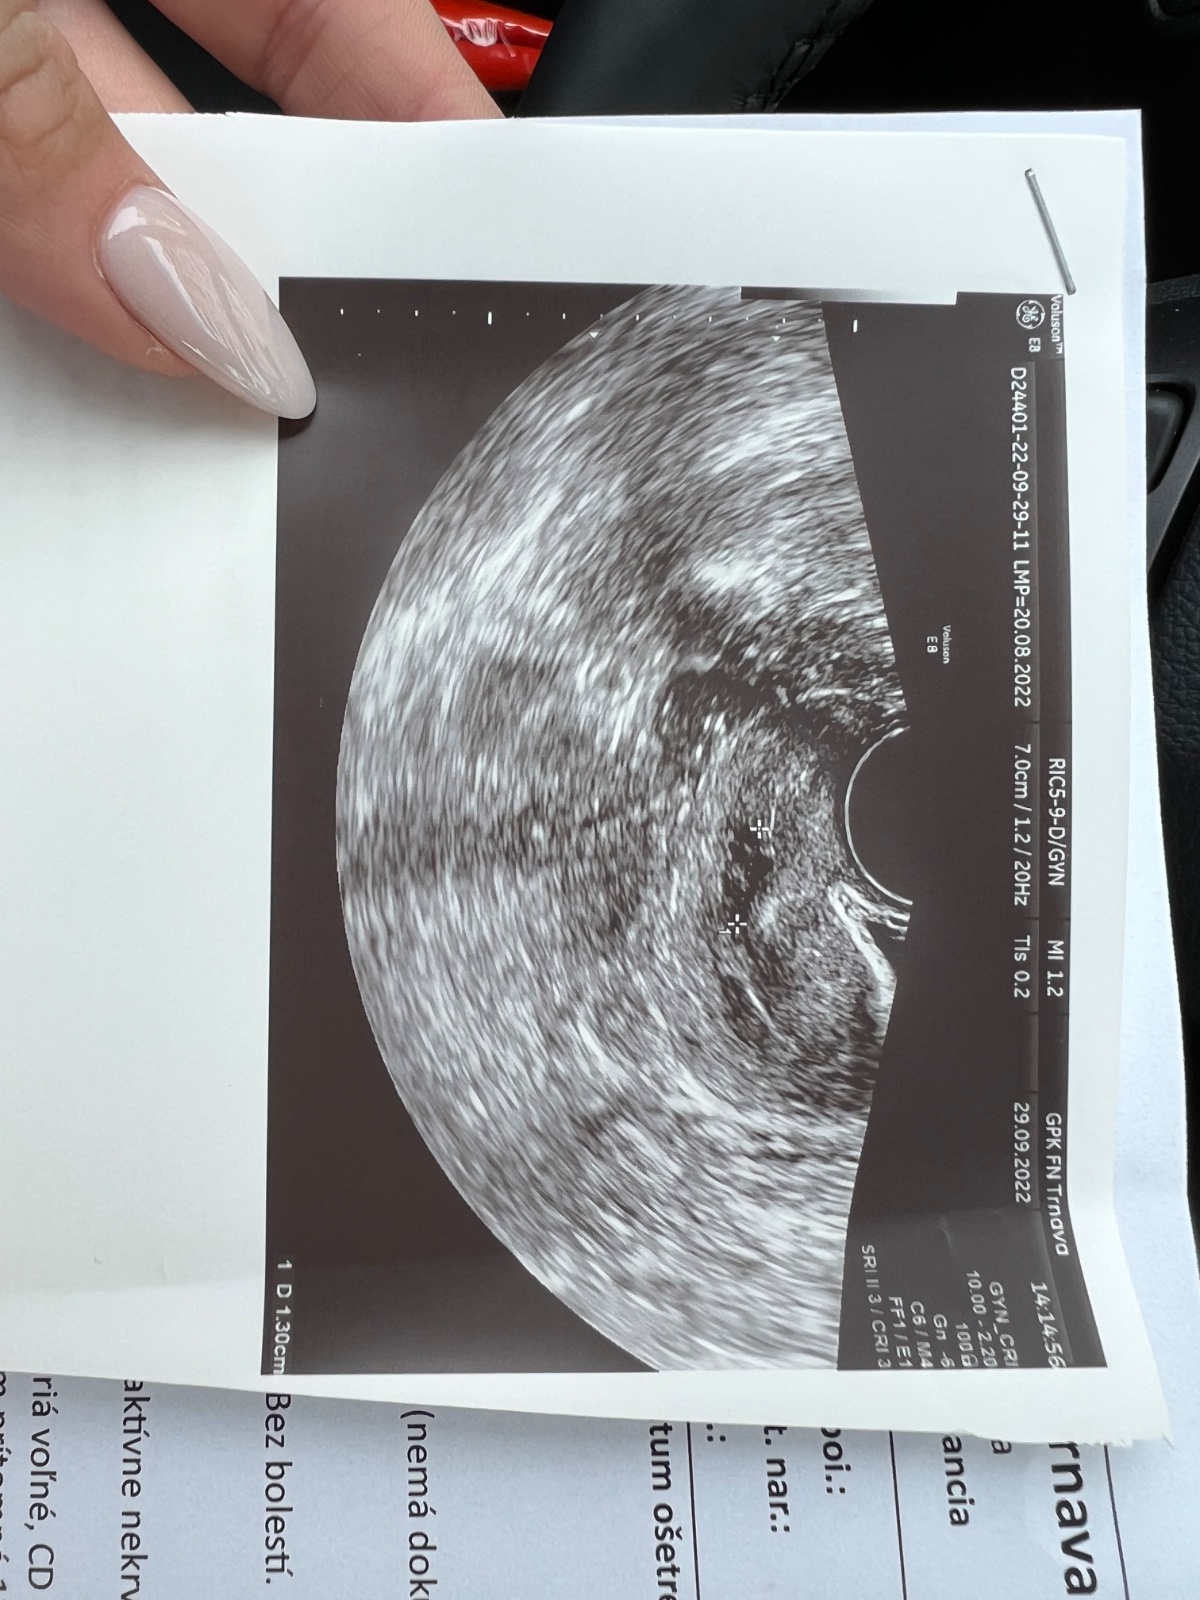

Vidíte tam niečo?

A co by sme tam mali alebo nemali vidiet? Vidime tam asi vsetci to iste. 🙃 Kazdopadne, nizko polozena placenta je na zaciatku tehotenstva normalny nalez, rastom sa bude posuvat vyssie (docca 20tt ma cas), teraz radsej dodrziavaj taky kludovejsi rezim, ked si krvacala. 🍀

@kikinka123456 nizko polozena placenta znamena, ze sa musis setrit, viac lezat, minimalna namaha, ziadny sex a nehladkaj si brusko(stimulujes tym kontrakcie) ... Je este velka sanca, ze sa posunie vyssie, casto sa to stava. Ak nie, tak sa budes musiet setrit az do konca, mozno aj lezat. Je to riziko, ale su aj horsie veci, neboj sa. Drzim palce.

@gabriela2952 no dnes som bola u svojej povedala že to včera podcenil a ona už dnes nič nevidela 6tt

Áno, ja mam tiež nízko položenú placentu, mam sa vyhýbať športu a nejakému traseniu, pri prípadnom krvácaní mam utekať ku dr.